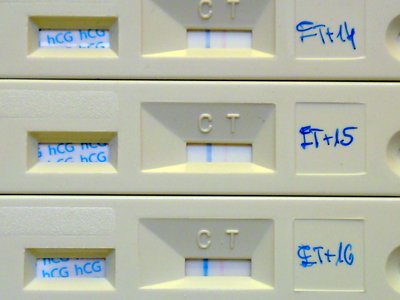

Tegnap este megint kitört a frász nálunk, este 7 körül épp vacsi előtt elkezdtem vérezni. Kórházba be, közben dokimat próbáltam hívni, de ki volt kapcsolva - utóbb kiderült, hogy épp műtött.

10 perc múlva visszajött a dokim és mondta, hogy szólt az ügyeletesnek, de nagyon elfoglalt, még legalább fél órát kell rá várni, úgyhogy menjünk fel a vizsgálóba és megnéz. Lényeg, hogy semmi gond nincsen, nem tudjuk mi okozta a vérzést (lehet egy kisebb erőlködéstől is, mivel épp mosdóban voltam amikor történt) vagy attól, hogy ha nem lennék terhes épp most mensiznék.